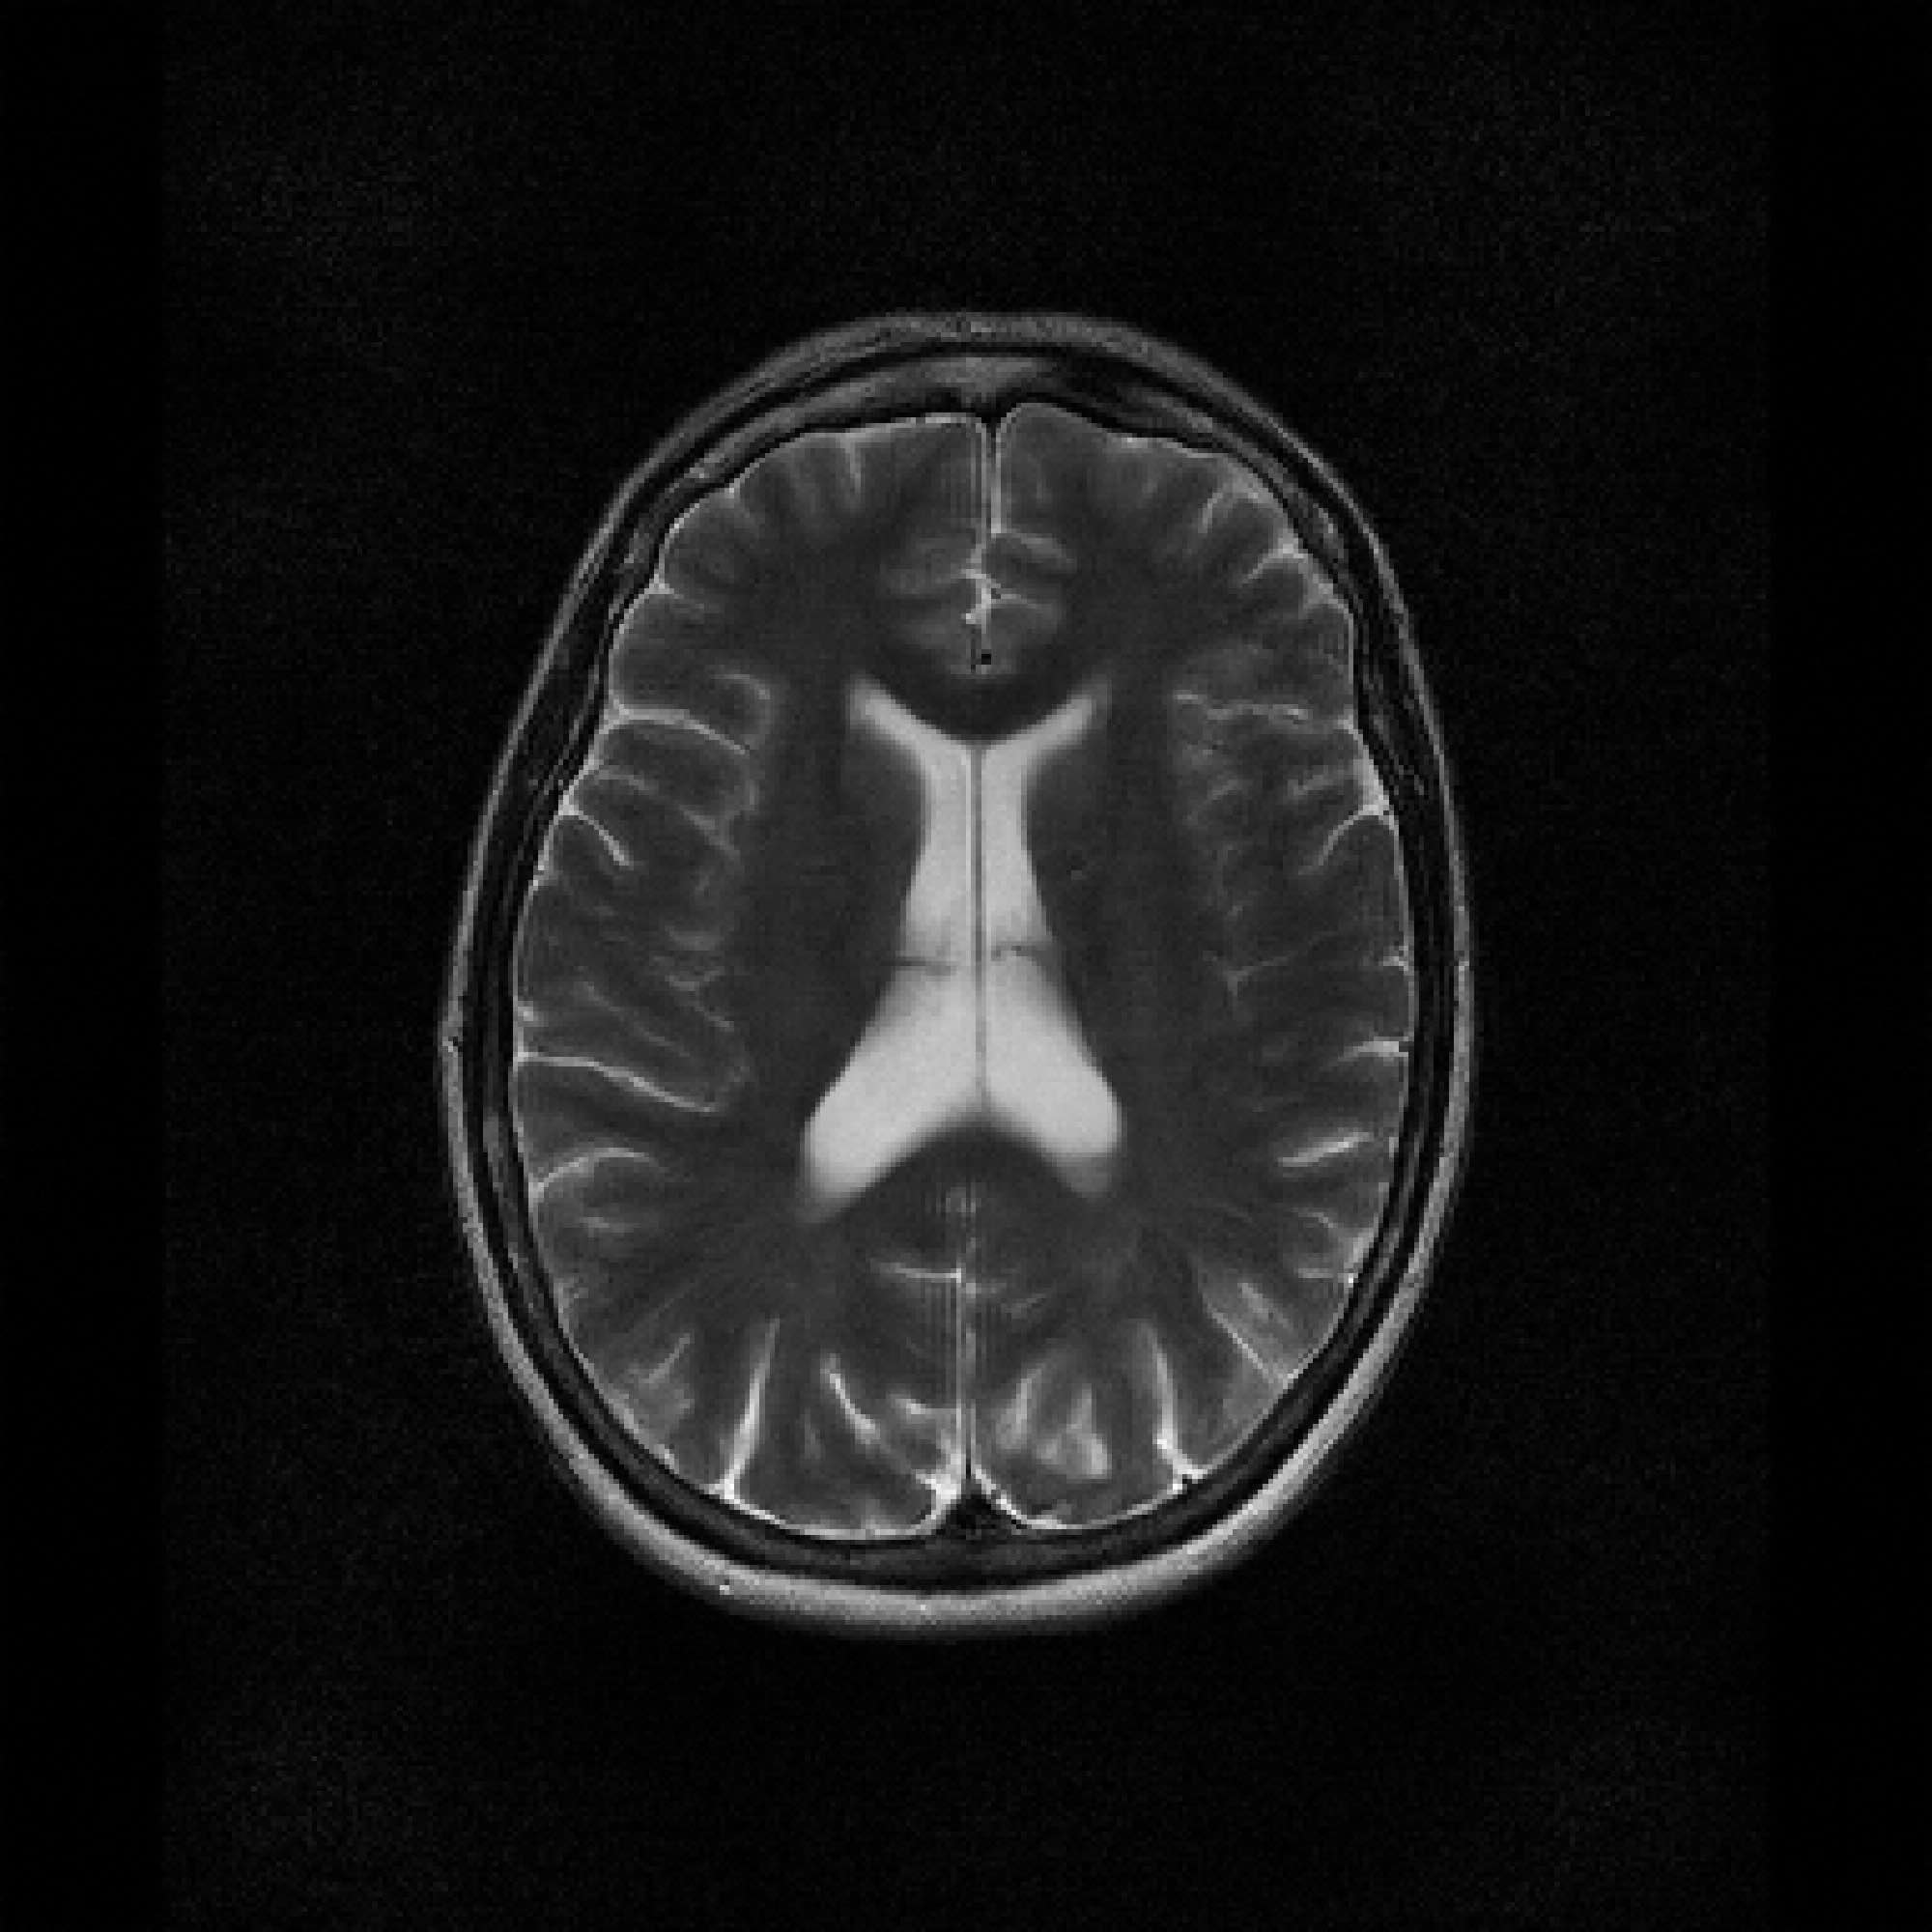

Refer to caption

Figure 2: Example MRI magnitude reconstructions with S=25S=25 training slices at acceleration (undersampling) factor R=7R=7. PaDIS-MRI reconstructions are sharper and more faithful to the fully-sampled ground truth. Insets are shown to the right to highlight detail.

Figure 2 provides a visual comparison of the reconstruction quality of each method on example slices. In reconstructions from the S=25,R=7S=25,R=7 models, FastMRI-EDM exhibits slightly more blurring and loss of fine structural details, particularly in regions with complex anatomical features. PaDIS-MRI, in contrast, preserves sharper boundaries and finer details. This enhanced data efficiency can be attributed to the patch-based prior’s ability to learn localized structural motifs more effectively from limited examples. Figure 6 in the Appendix shows similar reconstructions at S=200,R=7S=200,R=7 where FastMRI-EDM more closely approaches the performance of PaDIS-MRI but still struggles with highly detailed anatomy.